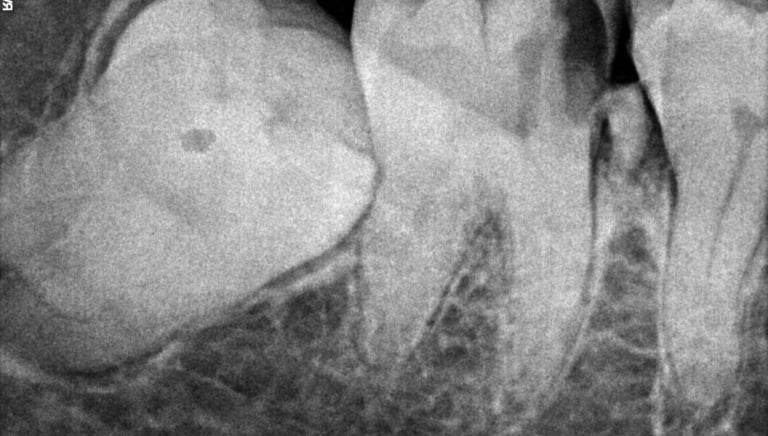

Q8. Do you use X-rays before tooth extraction?

Yes, dental X-rays are taken before extraction to assess the tooth position, root structure, and surrounding bone, ensuring safe and precise treatment.

All images shown here represent real clinical cases of teeth extractions done at our dental clinic with patient consent.

Illustrative images and similar real clinical cases requiring tooth extraction